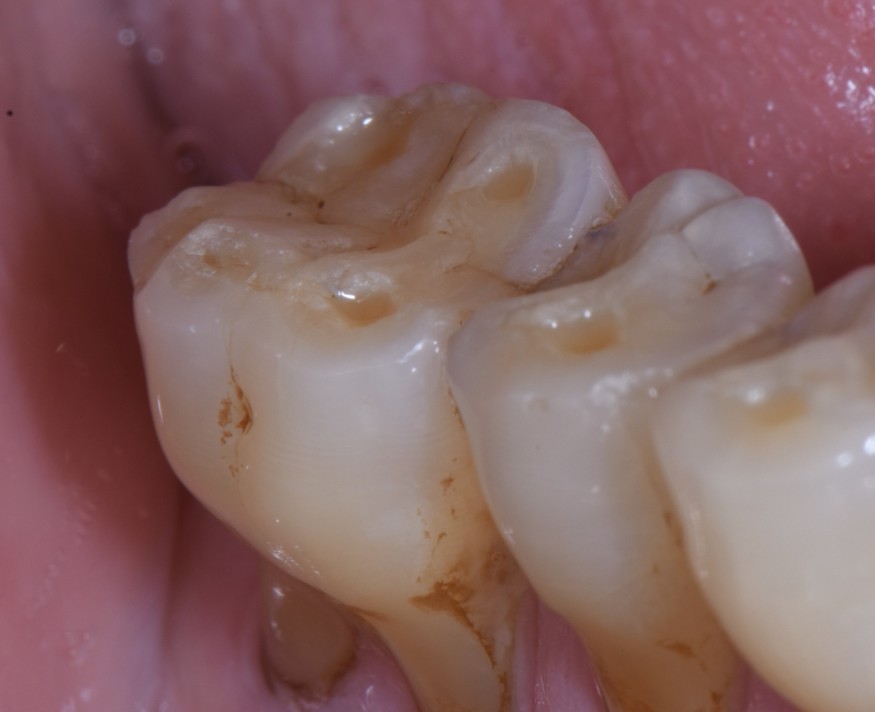

- Exposition dentinaire, due à la perte d’émail ou de cément, par abrasion (brossage traumatique), érosion (acides), attrition (bruxisme) (fig. 3-7), ou anomalies de structure (MIH**, amélogenèse imparfaite) [5].

(Source : HALEON Group) - Figure 3. Lésions érosives sévères associées à des lésions carieuses chez une patiente souffrant d’une addiction aux sodas.

(Crédit photo : Olivia Kérourédan) - Figure 4. Lésions érosives palatines au niveau du secteur incisivo-canin maxillaire, suggérant une acidité d’origine endogène.

(Crédit photo : Olivia Kérourédan) - Figure 5. Association de lésions d’usure d’origine érosive, abrasive et attritionnelle.